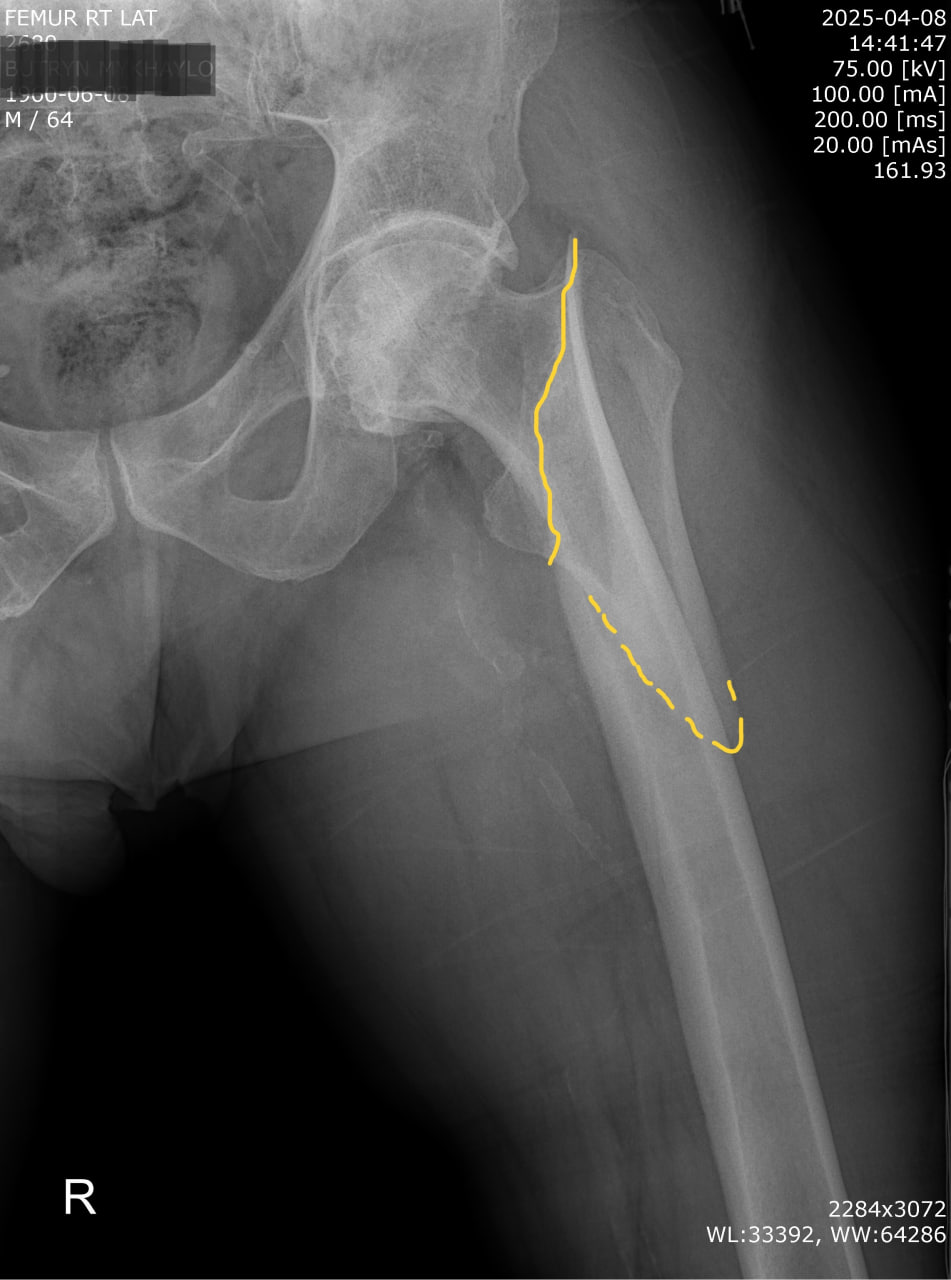

Пацієнт Б., 64 роки. Побутова травма — падіння з висоти власного зросту. Звернувся до травмпункту приймального відділення КНП ТМР «Теребовлянська міська лікарня». Після обстеження встановлено діагноз: закритий підвертельний перелом правої стегнової кістки зі зміщенням уламків.

Обсяг операції включав:

– анатомічну репозицію уламків,

– серкляжну фіксацію,

– інтрамедулярну фіксацію стрижнем PFN-A Long (Proximal Femoral Nail Antirotation) — «золотий стандарт» лікування підвертельних переломів.